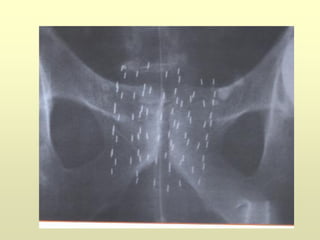

ETR y Biopsia

Madrid

Hospital Universitario

12 de Octubre